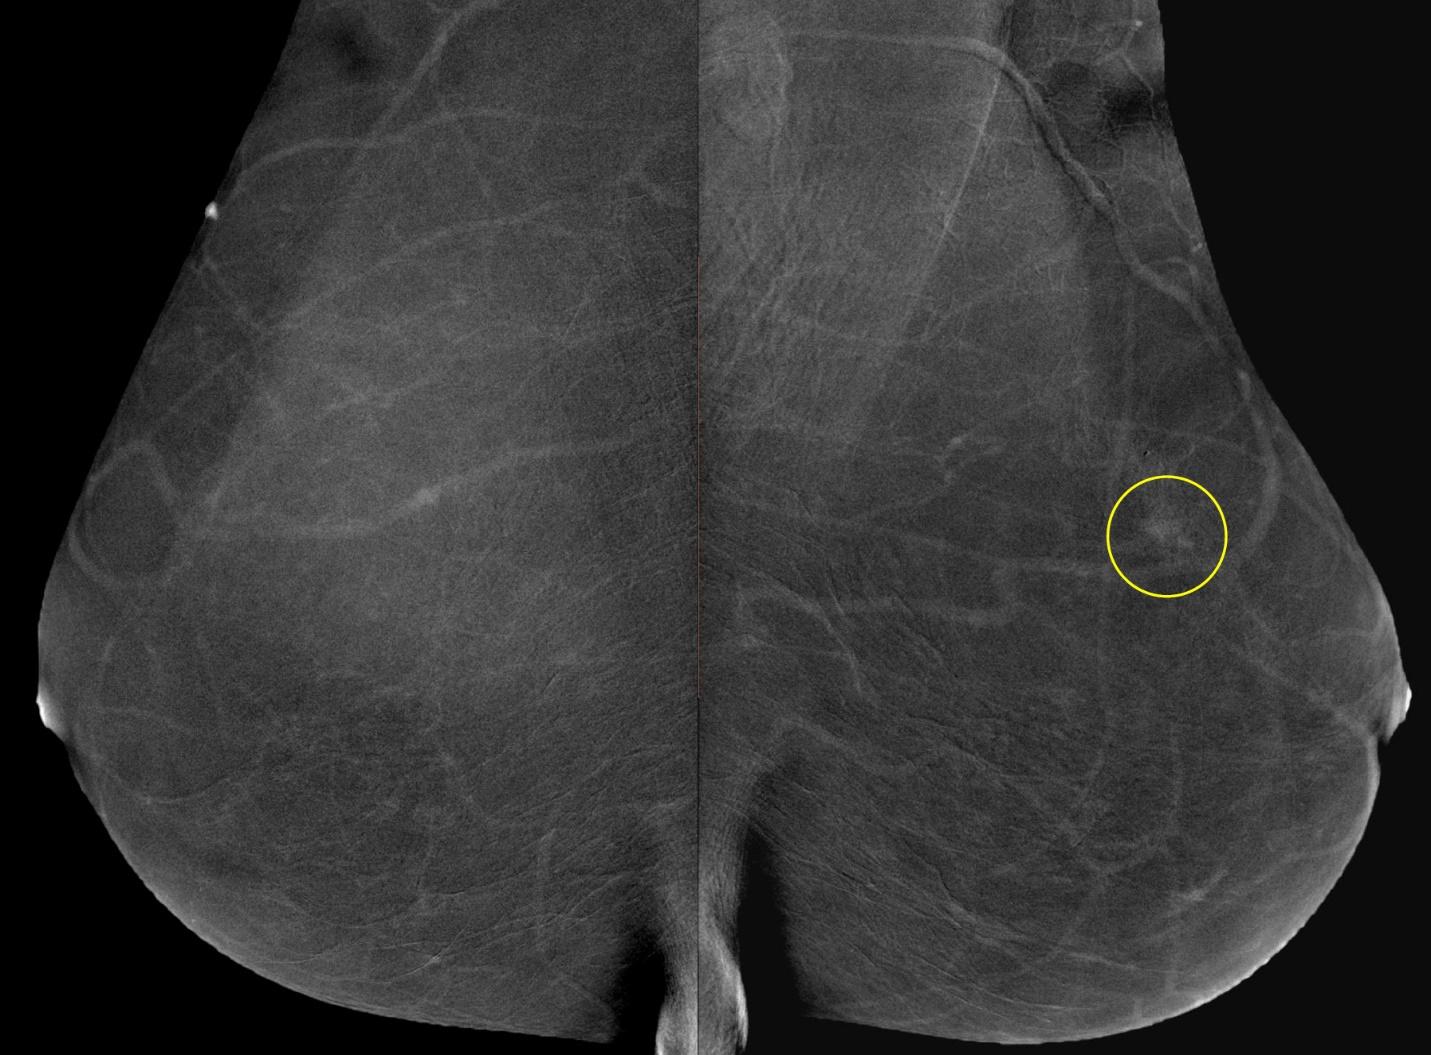

Шаг 8. Нужна ли функция цифрового томосинтеза (DBT)?